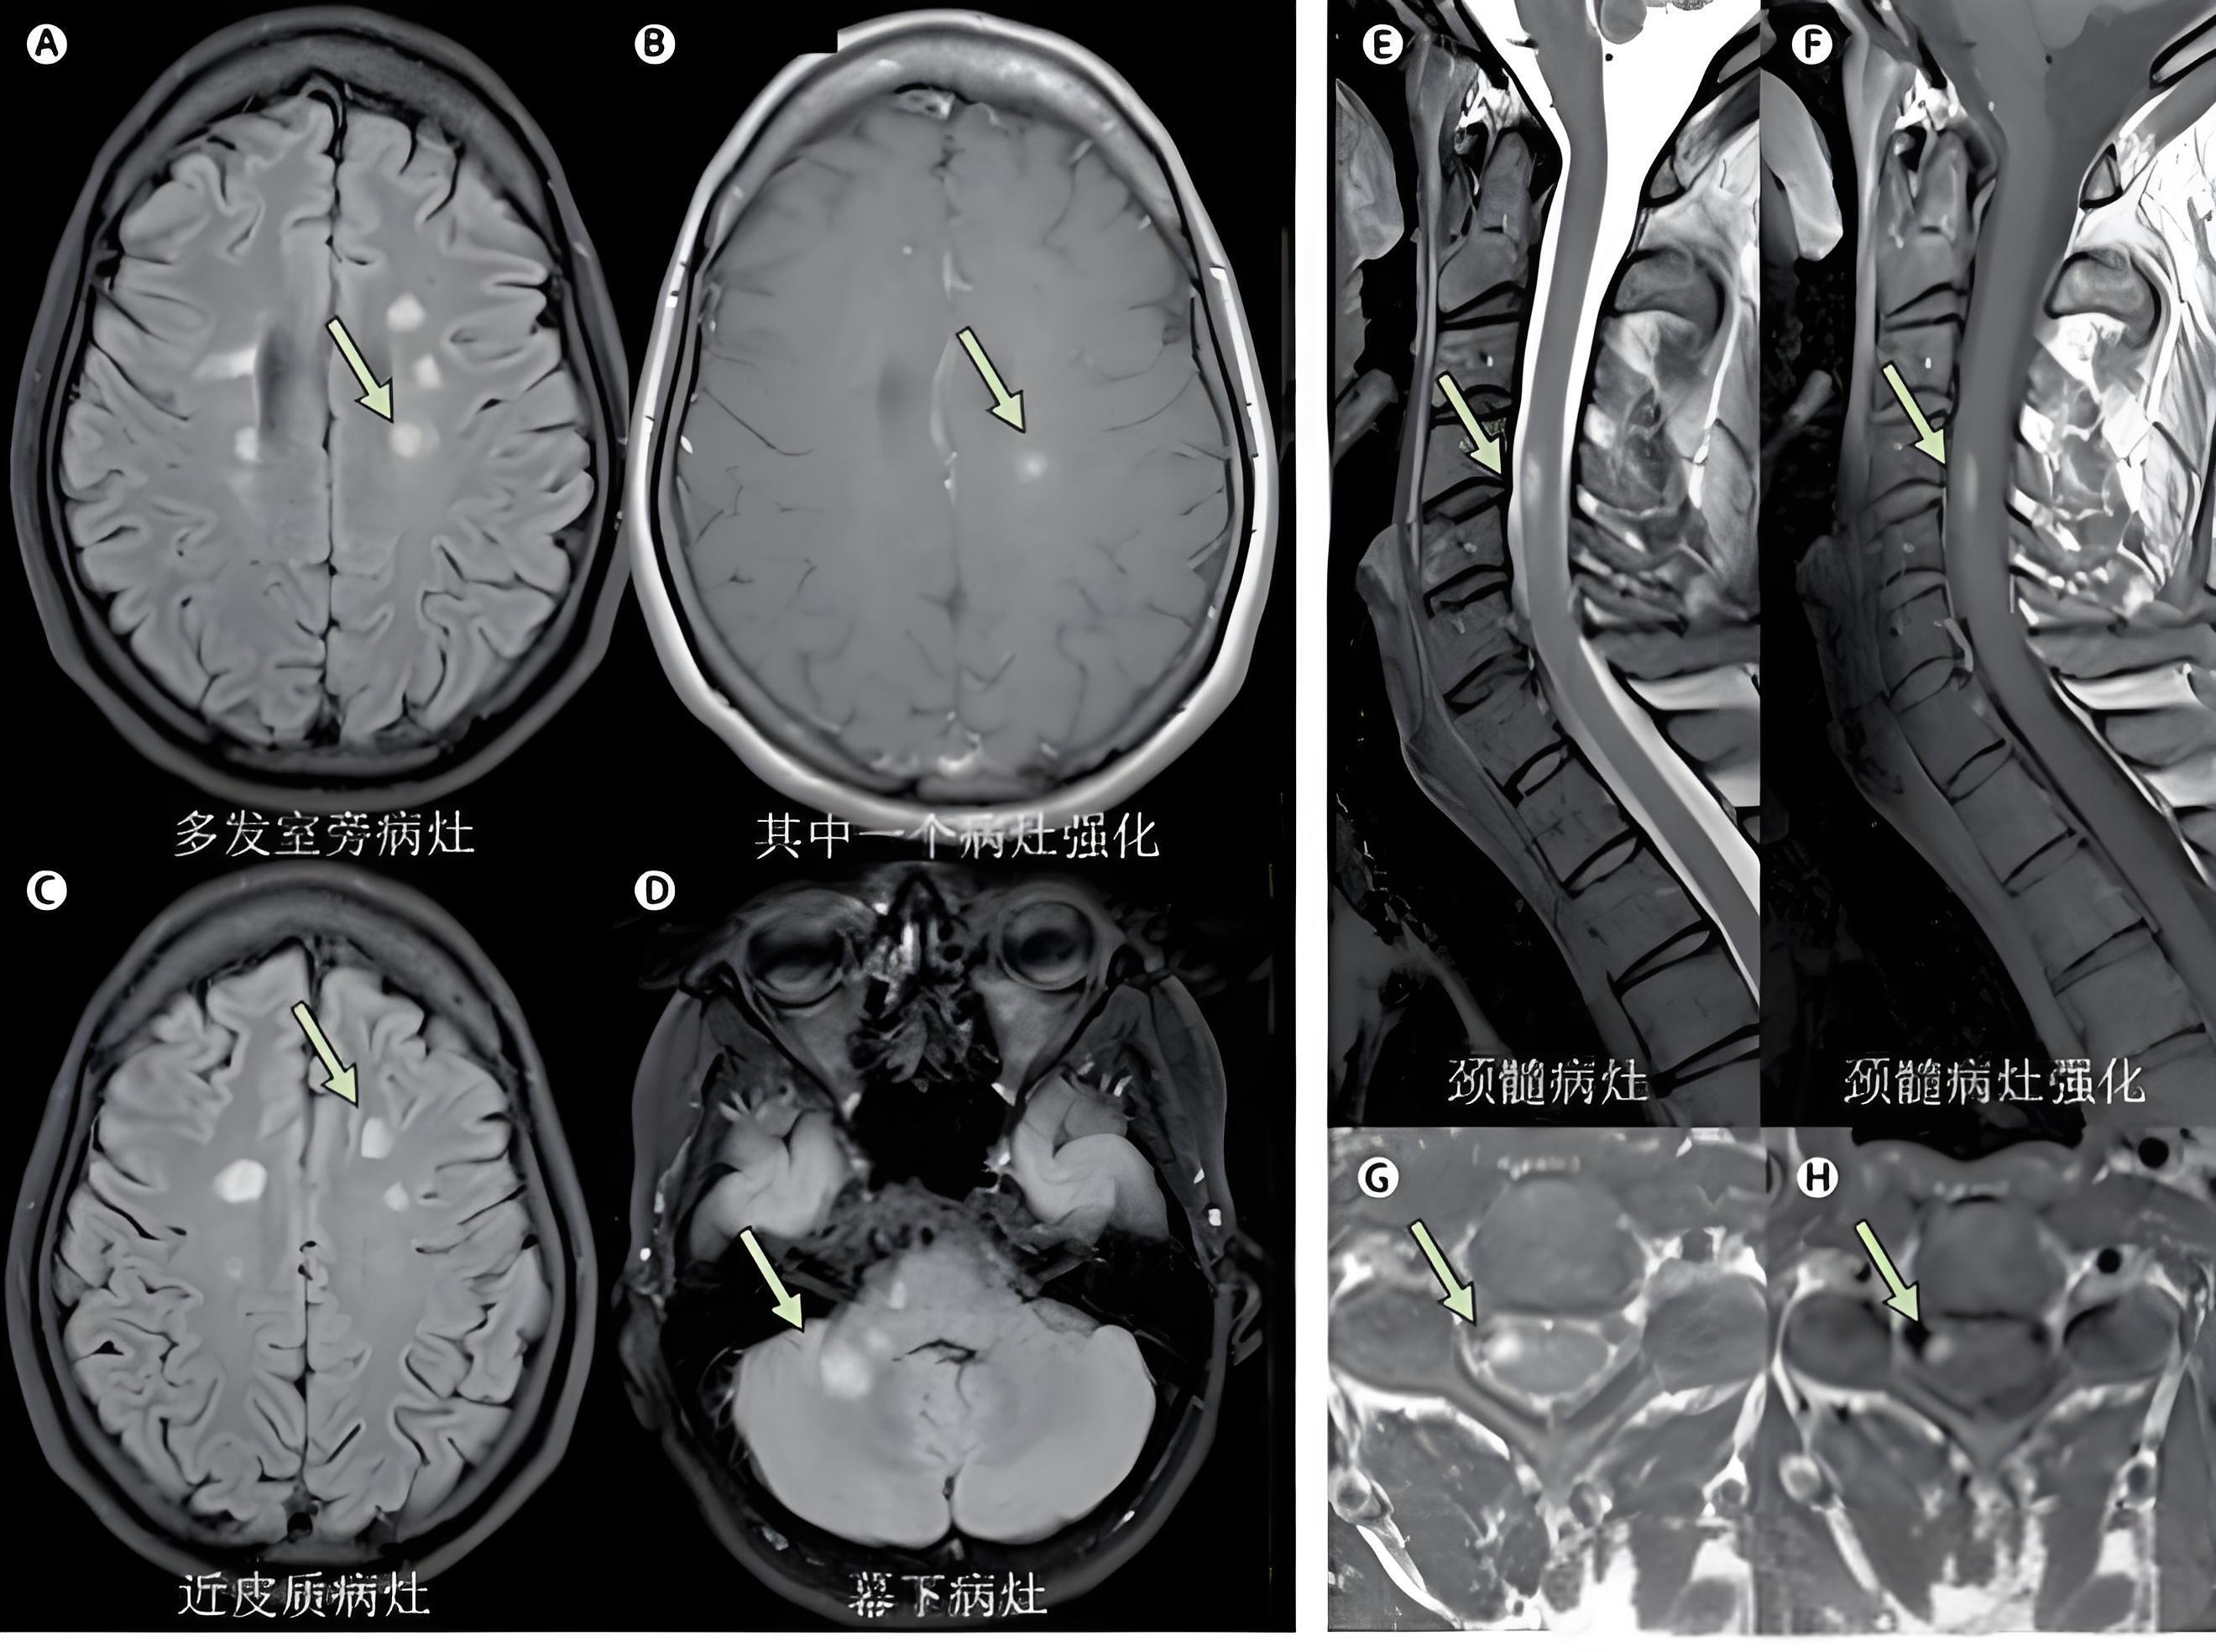

作為深耕神經(jīng)免疫領域的醫(yī)學工作者,今天帶您用10分鐘理清多發(fā)性硬化(MS)的鑒別困局——這不是非黑即白的判斷題,而是一場需要精準拼圖的醫(yī)學推理。關鍵鑒別點:這些疾病會與MS“共享癥狀“1.視神經(jīng)脊髓炎譜系疾病(NMOSD)偽裝破綻:AQP4-IgG抗體陽性(70%患者)經(jīng)典特征:視神經(jīng)炎+縱向延伸脊髓炎(MRI顯示≥3個椎體節(jié)段病變)治療警示:部分MS治療藥物可能加重病情2.萊姆病神經(jīng)型暴露線索:蜱蟲叮咬史+游走性紅斑血清學實錘:ELISA/Westernblot陽性反轉劇情:抗生素治療可顯著改善3.系統(tǒng)性紅斑狼瘡(神經(jīng)精神狼瘡)全身警報:蝶形紅斑/關節(jié)炎/腎病等多系統(tǒng)受累實驗室告密:抗核抗體(ANA)+抗雙鏈DNA抗體陽性影像差異:MRI病灶多位于小血管分布區(qū)4.維生素B12缺乏性脊髓病沉默幫兇:長期素食/胃腸術后/惡性貧血血液證據(jù):血清維生素B12<200pg/mL治療彩蛋:及時補充可逆轉部分癥狀診斷三階地圖第一關·臨床拼圖記錄癥狀時空分布(MS需滿足“時間+空間多發(fā)性“)第二關·影像偵查腦/脊髓MRI尋找典型病灶:側腦室旁、皮層下、胼胝體、腦干第三關·實驗室驗證腰穿:腦脊液寡克隆區(qū)帶(OCB)血液:排除感染/代謝/免疫性疾病給讀者的科學備忘錄警惕“三不癥狀“:不明原因視力驟降、肢體麻木呈“襪套樣“分布、突發(fā)性平衡障礙診斷沒有快捷鍵:從首次發(fā)作到確診平均需1.5-2年(需排除30+種相似疾?。┲委煏r間窗:早期啟用疾病修正治療(DMT)可降低80%年復發(fā)率劃重點的科學態(tài)度多發(fā)性硬化的診斷如同破解動態(tài)密碼——既需要捕捉癥狀與影像的時空關聯(lián)性,又必須嚴謹排除所有“模仿者“?,F(xiàn)代神經(jīng)免疫學已讓MS從“不治之癥“轉變?yōu)榭煽芈圆?,但正確診斷始終是治療的第一塊基石。(本文適用于科普交流,個體診療請以正規(guī)醫(yī)療機構方案為準)

多發(fā)性硬化(MS)是一種中樞神經(jīng)系統(tǒng)慢性炎性脫髓鞘性疾病,其病情演變不可預測。MS患者早期多表現(xiàn)為復發(fā)-緩解病程,即反復出現(xiàn)新的局灶性神經(jīng)系統(tǒng)癥狀和體征,經(jīng)過激素等治療甚至未治療自然恢復。但隨著病程延長,大部分患者復發(fā)時激素治療效果下降,甚至不復發(fā)也會出現(xiàn)緩慢的神經(jīng)功能障礙如行走困難和不穩(wěn)、認知下降等,即可能轉變?yōu)檫M展型MS。從MS首次發(fā)病到進展型MS的時間不等,40%患者6-10年內(nèi),一般10-20年左右。這可能和MS早期以炎性反應為主,隨后發(fā)生不依賴炎性反應的神經(jīng)退行性改變有關。轉變?yōu)檫M展型MS的危險因素很多,如EDSS評分3分以上、高復發(fā)頻率、腦灰質萎縮、更多的腦內(nèi)T2病灶等可預測MS進展,但早期使用疾病修正藥物能預防復發(fā)、減少長期的神經(jīng)惡化和繼發(fā)進展的風險。盡管目前治療MS的疾病修正藥物很多,包括口服、皮下注射以及靜脈輸液藥物,大多數(shù)是治療復發(fā)緩解型MS,一旦進入進展期,治療相當困難。故目前許多國外MS指南均推薦:一旦MS診斷明確,盡可能早期使用疾病修正藥物。但由于這些藥物價格昂貴,需要長期使用,并且有一定副作用,很多患者經(jīng)濟因素等原因,而采取等待看看的策略而延緩治療。盡管MS患者隨著發(fā)病時間的延長,會轉為進展型MS。但MS個體的自然病程不可預料。有報道10-15%MS患者發(fā)病多年并不導致嚴重殘疾。因此對于發(fā)作時癥狀體征輕微,經(jīng)過治療能完全緩解,頭部和脊髓病灶不多,經(jīng)濟情況不允許者可以采取暫時不用藥物而采取等待看看的策略,但必須每6-12月進行神經(jīng)和影像學檢評估。然而對于復發(fā)后不能完全恢復、復發(fā)時肢體癱瘓或小腦功能如走路不穩(wěn)、共濟失調(diào)嚴重、既往2年內(nèi)2次以上復發(fā)、磁共振檢查腦內(nèi)多發(fā)強化病灶或10個以上T2高信號病灶患者盡早使用疾病修正藥物